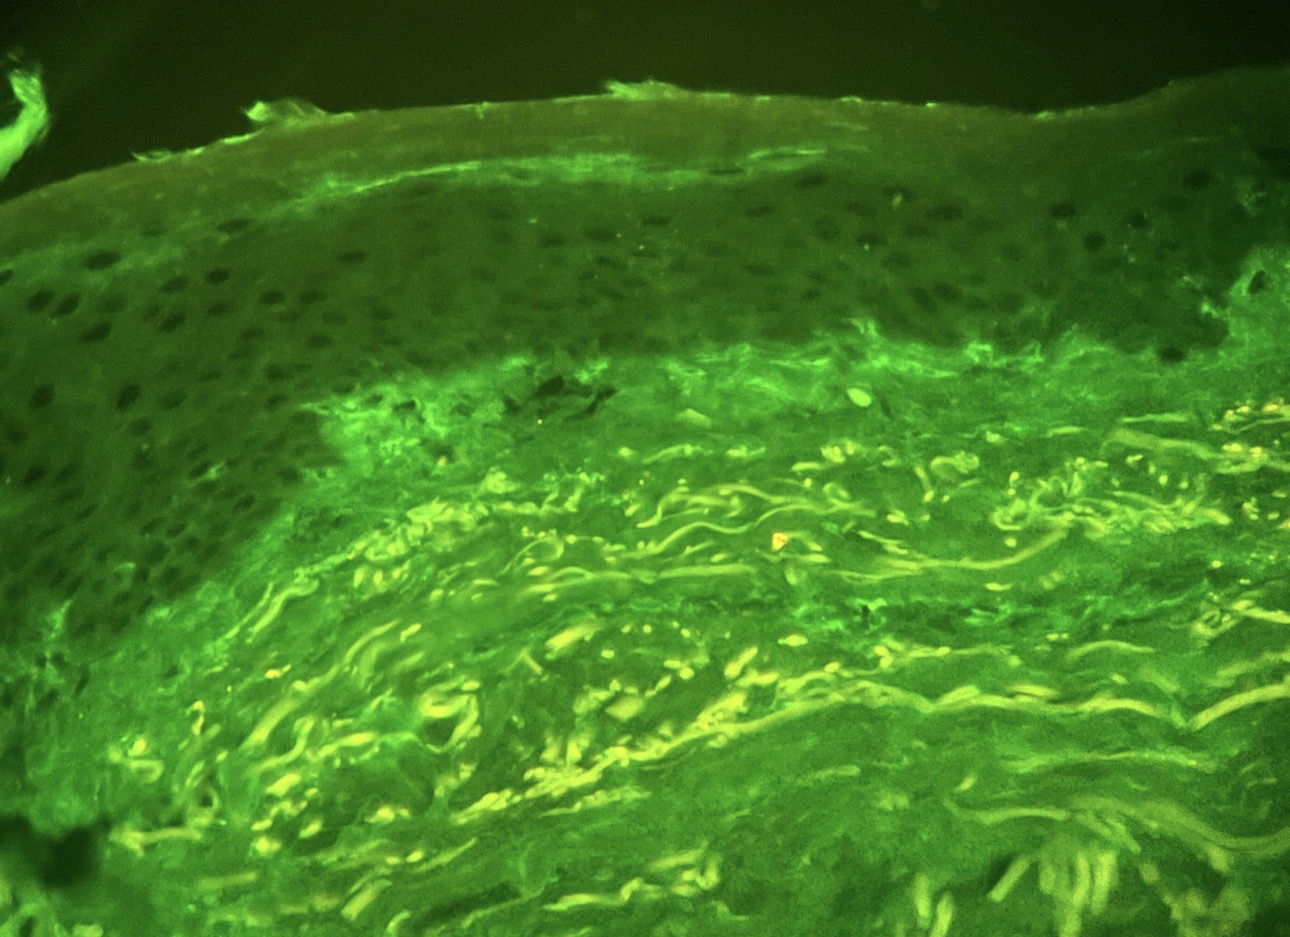

Tecnología de punta, con criterio Patología digital, inmunohistoquímica e inmunofluorescencia automatizadas, respaldadas por experiencia humana calificada.